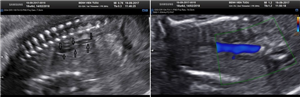

Ca lâm sàng siêu âm thai: Bất sản thận